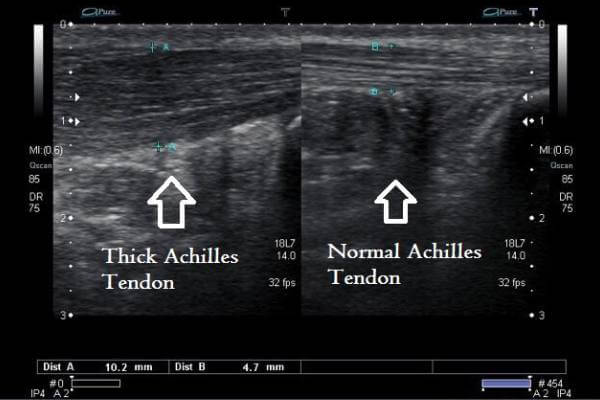

At the Ankle, Foot and Orthotic Centre we are able to provide additional information about the presence of Midportion Achilles Tendinopathy or Insertional Achilles Tendinopathy with ultrasound imaging.

Typically, someone with Midportion Achilles will have a thicker disorganised midportion area in the midportion of the Achilles. This is in addition to extra blood vessels in the tendon.